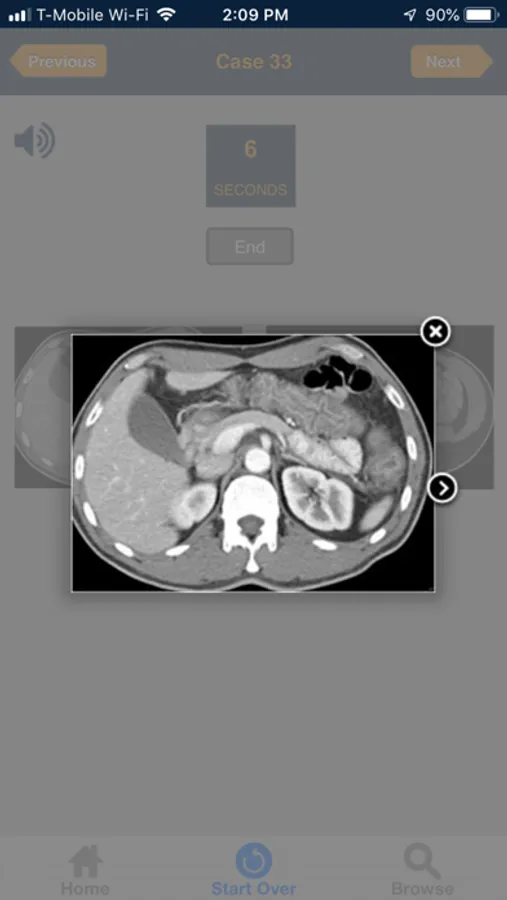

This App includes radiology images for 60 emergency cases that users must diagnose in 10 minutes. Each case is presented as an unknown. You have 10 seconds to make the diagnosis, before the answer is provided.